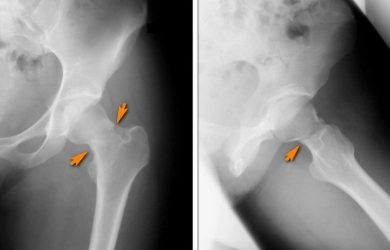

Вивихи ендопротезів – друга за частотою причина ревізійних втручань (4 місце за статистикою) після асептичного розхитування компонентів ендопротезів